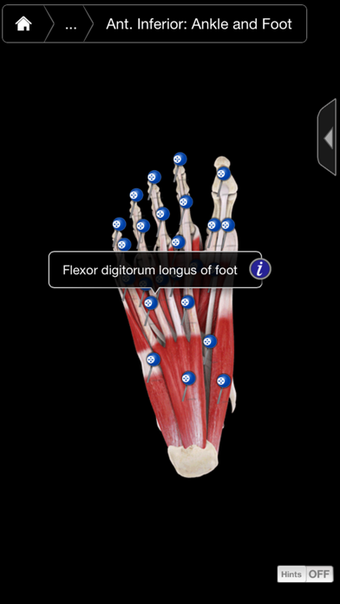

Muscle System Pro III - IPhoneเป็นโปรแกรมเวอร์ชันเต็มสำหรับ iPhone ซึ่งอยู่ในหมวดหมู่ 'ยา'

เกี่ยวกับ Muscle System Pro III - IPhone สำหรับ iPhone

Muscle System Pro III - IPhone พร้อมใช้งานสำหรับ iOS 12.1.2 ขึ้นไป เวอร์ชันปัจจุบันของโปรแกรมคือ 3.8.2 และคุณสามารถเรียกใช้ได้ในภาษาอังกฤษเท่านั้น